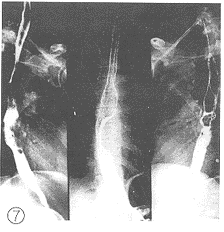

2.1 X线影像比较:每例患者在术前加速放射治疗结束后第2d及第14d分别两次摄食管钡餐造影片。由放射科、放射治疗科、胸外科3名副主任医师以上的人员读片,读片前用胶布粘住每例患者的摄片的日期,再进行“多盲法”对比观察、记录。评判标准按1981年第三届全国放射学术会议(郑州)治疗组通过的食管癌放射治疗后X线诊断标准分为4级。Ⅰ级:病变完全消失,食管壁软而光滑,蠕动及扩张良好,粘膜纹理清楚可见(图1、 2);Ⅱ级:病变基本消失,食管壁规则,钡剂能顺利通过,但管壁仍僵直或狭窄,蠕动未恢复,粘膜仍增粗(图3、 4);Ⅲ级:病变明显好转,食管病灶退缩一半以上,没有明显扭曲、成角以及突出腔外的溃疡,稠的钡剂能通过(图5、 6);Ⅳ级:病变残留或恶化,病灶消退不到一半或成角,扭曲明显或有突出腔外的溃疡,钡剂通过极差(图7、 8)。118例术前加速放射治疗后不同时间的X线影像变化结果中,从Ⅲ、Ⅳ级病例上升为Ⅱ、Ⅲ级者最多,分别达 37.8%(17/45)和43.8%(7/16);但未发现越级上升和降级病例。

图7 食管中段癌髓质型

图8 放射治疗14d仍示病灶残留,病灶消退不足1/2。